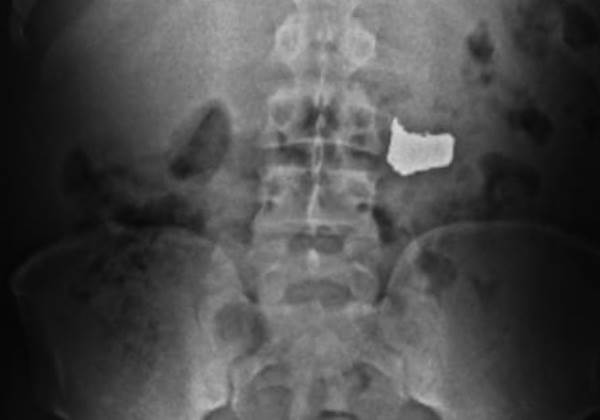

De imediato, as guarnições da 11ª CIPM encaminharam o suspeito para a UPA dos Barris. Os médicos realizaram um exame de raio-X e atestaram a presença da corrente.